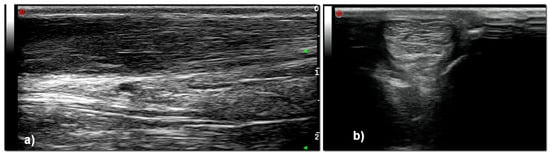

- Grade 1: Normal tendon with parallel fibers and homogeneous architecture

- Grade 2: Enlarged tendon with bowed margins and homogeneous architecture

- Grade 3: Hypoechoic area with or without tendon enlargement and bowed margins